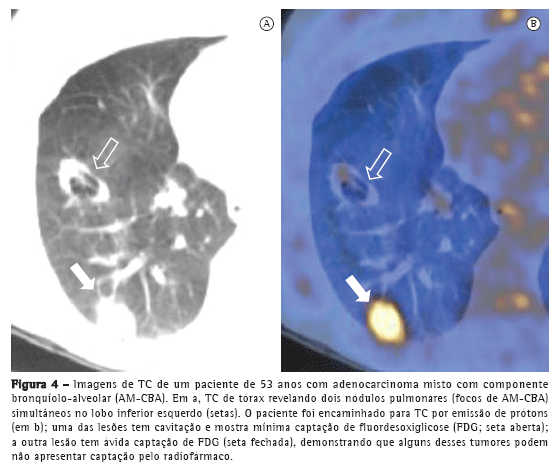

A positron emission tomography (PET, tomografia por emissão de prótons) é tida como ferramenta fundamental no estadiamento, tratamento e seguimento de neoplasias pulmonares (Figura 4). Entretanto, deve-se enfatizar que os CBA puros podem não demonstrar hiperconcentração de 18F fluordesoxiglicose (FDG),(6) dado que esses tumores são usualmente indolentes, de crescimento lento e bem diferenciados. Logo, a ausência de captação do FDG não exclui a possibilidade de neoplasia, tais como CBA, pequenas lesões ou neoplasias indolentes. Martins et al.(17) estudaram a acurácia diagnóstica da PET na avaliação de nódulos pulmonares solitários e, dentre os 32 pacientes estudados, obtiveram somente um resultado falso-negativo, cujo diagnóstico final foi de CBA. Sendo assim, a análise do aspecto tomográfico é mandatória para o diagnóstico (Figura 5).